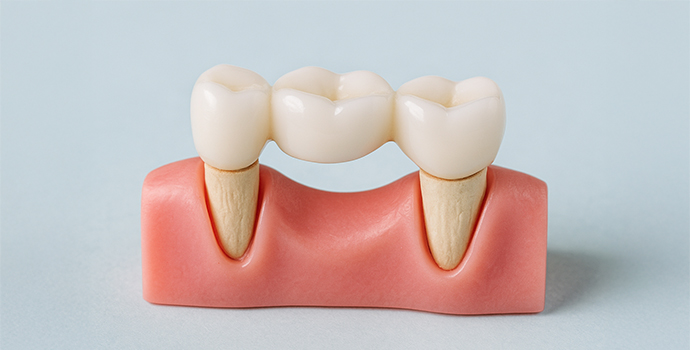

失った歯の機能と見た目を回復させる治療法が「ブリッジ治療」です。歯を失った箇所の両隣にある健康な歯を削って土台として活用し、橋を架けるように人工歯を固定します。

ブリッジ治療では、失った歯の部分をダミーの歯で補うことにより、天然歯に近い噛み心地を実現できます。入れ歯のような取り外しの手間がなく、固定式のため安定性に優れ、食事や会話時の違和感も入れ歯と比較して少なくなります。また、インプラント治療で必要な歯茎の切開や骨を削る外科的な手術を伴わないため、患者様の身体への負担を軽減できる治療法です。